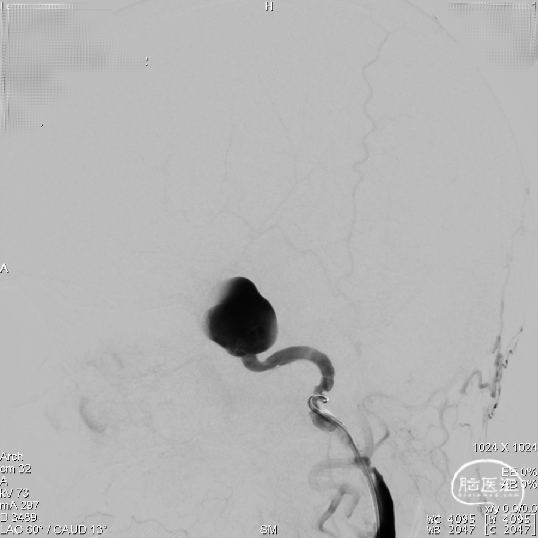

路图显示患者颈内动脉血管迂曲,瘤口处载瘤动脉呈现”S”反角弯;为使支架导管能顺利到达动脉瘤远端区域,采用囊内“成襻/解襻技术”,通过交换导丝带栓塞微导管到达动脉瘤远端,交换Fastrack-27支架微导管到达M1段。

支架定位:

输送支架到达支架微导管远端,缓慢回撤Fastrack-27支架微导管使支架头端打开呈“V”型,整体回撤支架系统定位于颈内动脉分叉段下约2mm位置进行锚定。

支架释放:

因载瘤动脉较为迂曲,为使支架头端锚定牢固, 4.5mmx45mm Tubridge血流导向密网支架前端1/3处采用稳定支撑系统逐步缓慢给张释放支架,使支架前端充分打开并与血管壁充分贴合。

当Tubridge血流导向密网支架释放到瘤颈弯段位置时,既要保障支架能充分打开、又要保障近端导管张力可控防止支架整体疝入动脉瘤囊内。因此采用节段性“推拉释放技术”既局部给张/松张,来回推挤技术释放支架,并通过持续造影观察支架打开、贴壁及血流转向效果等情况。

通过减影、显影所示,4.5mmx45mm Tubridge血流导向密网支架尾端长度充分且足够,为达到预设计的释放落脚点位置,支架尾端释放采用“推挤+减张瞬间释放技术”通过支架张力使尾端快速打开。

造影检查:

支架打开后即刻造影判断Tubridge血流导向密网支架已充分打开、贴合,同时可见瘤囊内造影剂滞留明显。